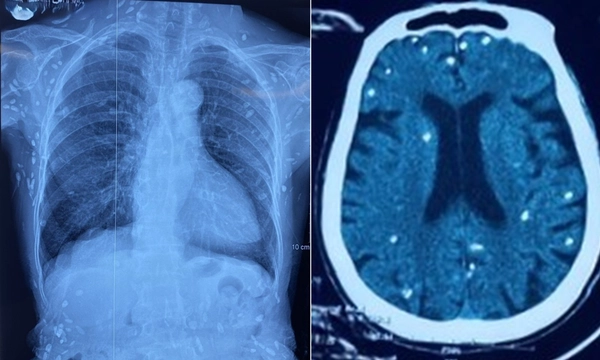

Nữ bệnh nhân (sinh năm 1948) được chuyển lên từ tuyến trước vì rối loạn ý thức đe dọa suy hô hấp, hình ảnh cắt lớp vi tính sọ não và X-quang ngực cho thấy rất nhiều nốt cản quang trong nhu mô não và dưới da vùng ngực-bụng.

Một vài u cục với kích thước tương ứng có thể sờ thấy dưới da vùng ngực và cánh tay của bệnh nhân.

Mặc dù xét nghiệm kháng thể IgM với sán dây heo âm tính, các tổn thương trên X-quang gợi ý bệnh nhân trước đây bị nhiễm ấu trùng sán dây heo, sau đó các nang sán trở nên vôi hóa và tồn tại lâu dài trong tổ chức.

Nang sán dây heo có thể tự thoái hóa hoặc bị vôi hóa, tạo nên nhiều hình ảnh cản quang phát hiện được trên phim X-quang như trường hợp bệnh nhân trên.